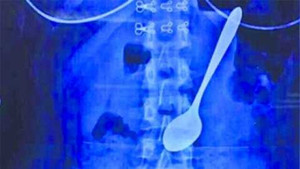

Một sinh viên ở Trung Quốc đã nuốt cả chiếc thìa dài 14cm vào bụng khi đang ăn kem.